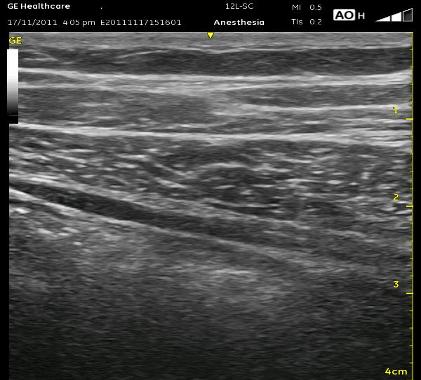

The below ultrasound image can not demonstrate the relative ease of determining the exact location of each of the muscular layers because you do not see the bowels moving and do not get to orient yourself by starting at the rectus muscle. In this image, the thickest layer is the internal oblique muscle, and the dark area just below that is the transversus abdominus muscle. The white line between these muscles is the fascia representing the TAP. Below the transversus abdominus muscle is a wide shimmering white area which represents the bowels. The II/IH nerves are seen as a white thickened area in the TAP fascia at about the middle of the image.